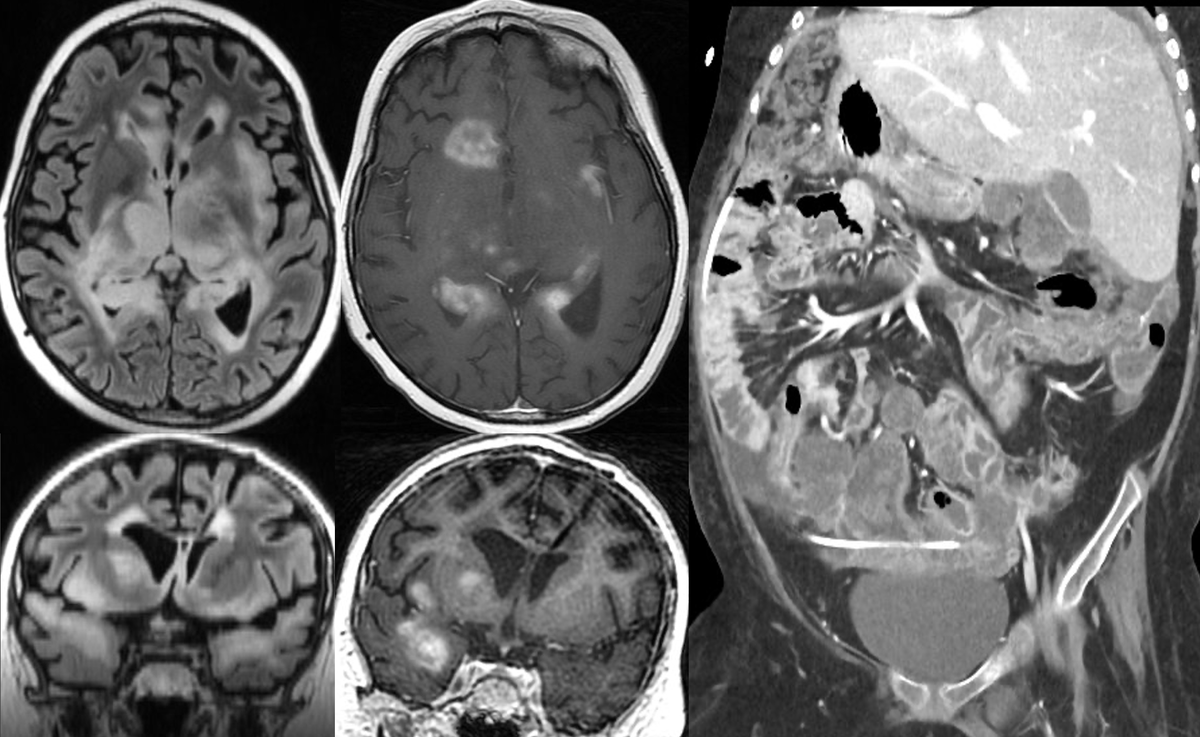

There are meningiomas hiding in plain sight... We just need the tools to find them. Here are two cases of meningiomas hiding in the dural venous sinuses. Easy to miss, but ASL perfusion makes them jump off of the screen. Are you using routine perfusion imaging for brain tumors?

Sometimes its scary when a neuroradiologist tries to look inside the abdomen, but sometimes it can make the diagnosis! Whats going on here?